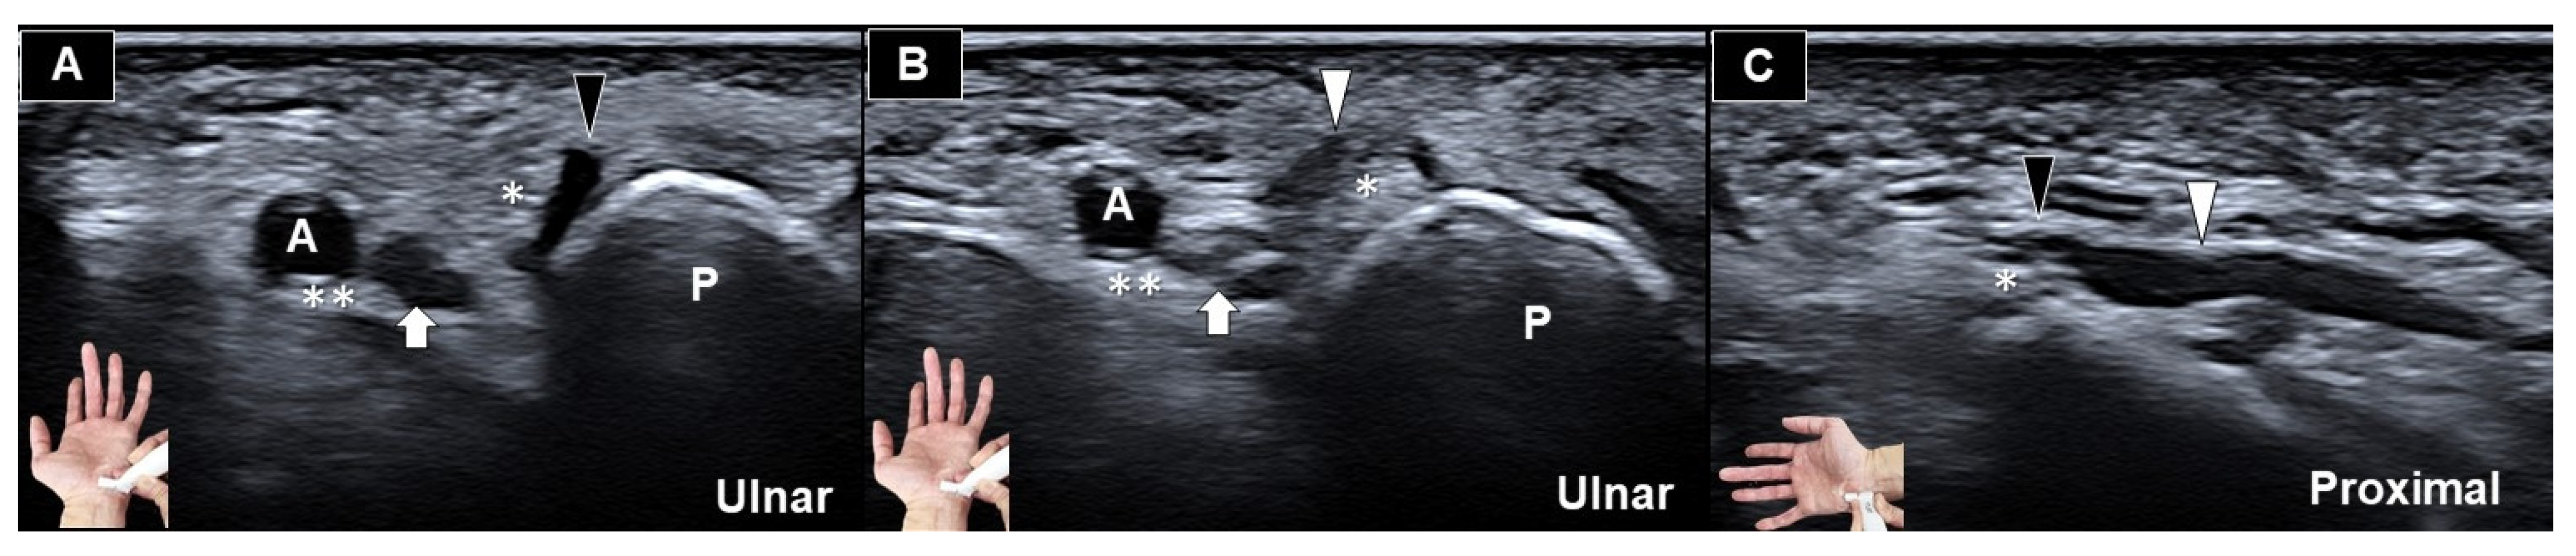

Ultrasonograhic Identification of the Entrapment of a Transligamentous Sensory Branch of the Ulnar Nerve

- Vargas, C.R.; Chepla, K.J. Report of a Transligamentous Ulnar Nerve Sensory Branch. Hand 2020, 15, NP11–NP13. [Google Scholar] [CrossRef] [PubMed]